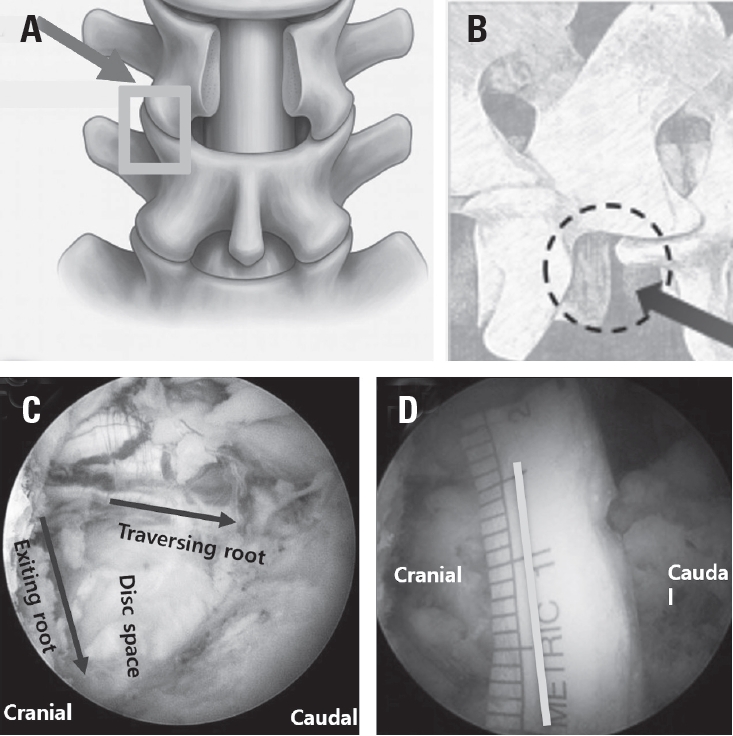

Fig. 2.

Schematic illustration of the extraforaminal working corridor for biportal endoscopic revision extraforaminal lumbar interbody fusion (BE-REFLIF) in a previously decompressed segment. (A) Targeting of the remnant inferior articular process (IAP) and the superior articular process (SAP) to define the bony boundaries of the working corridor. (B) Illustration of the established extraforaminal corridor used for interbody cage insertion. (C) Visualization of the opened disc space between the exiting nerve root and the traversing nerve root after adequate decompression. (D) Measurement of the distance between the traversing and exiting nerve roots, demonstrating a minimum required safety margin of 15 mm to allow safe insertion of the interbody cage.

The extraforaminal surgical corridor was developed by exposing the transverse process and advancing medially to the facet joint. The facet capsule was released, and the superior articular process was removed using a high-speed burr and chisel to maximize the acquisition of autologous bone graft. Subsequent flavectomy allowed visualization of Kambin’s triangle. Foraminal decompression was completed by resecting the medial aspect of the transverse process and residual bony structures adjacent to the exiting nerve root, ensuring adequate decompression and a safe working corridor (Fig. 2).

4) Disc space preparation

Through the extraforaminal portal and medial portal, annulotomy was performed, followed by disc removal using reamers and pituitary forceps. About 20 mm safety margin lateral to the traversing nerve root was maintained to accommodate a large-footprint cage. Endplate preparation was performed with angled curettes under direct endoscopic visualization, using the medial portals when necessary to inspect the endplate corners (Fig. 3). Sequential trials were used to restore disc height with minimal endplate violation. Bone graft material was introduced into the disc space via a funnel-type delivery device.